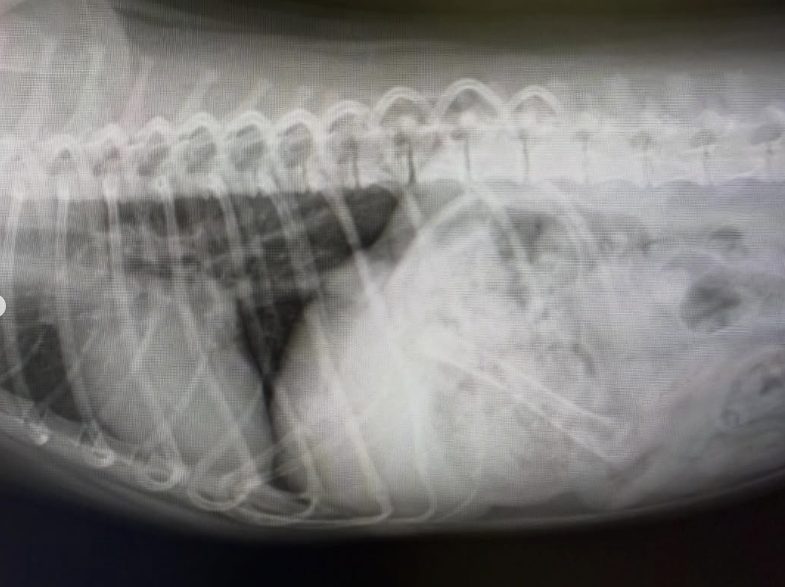

最初の画像の子は、吐くとの主訴で来院され、変なものは食べてないとの事でしたが、レントゲンで明らかに変なものがある。サイズ的にも内視鏡では難しいと判断して本日手術を実施。二枚目の画像のような木の実?のようなものが胃と腸にあり、腸では詰まってました。腸に穴開いたりしなくて良かった。